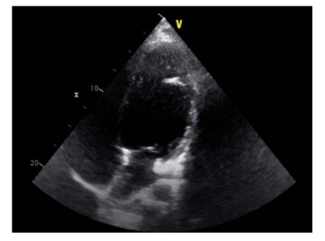

A 52-year-old man with multiple cardiovascular risk factors, including arterial hypertension and diabetes mellitus type II, was referred to our interventional cardiology unit because of a poor response to year-long treatment.